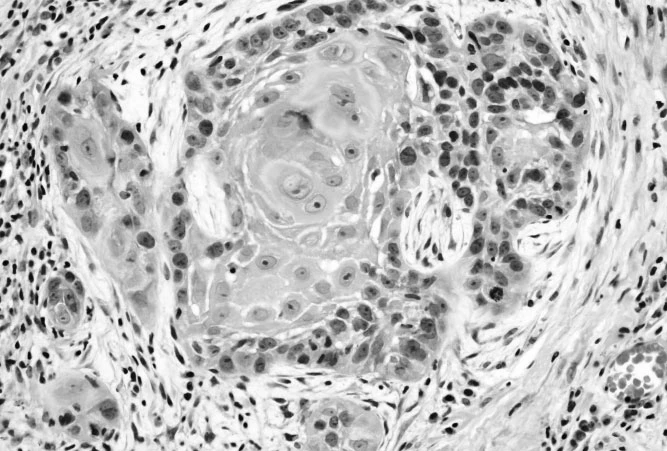

Carcinoma

Carcinoma is the most common type of cancer, and it originates from epithelial cells (cells that cover the inside and outside surfaces of the body).